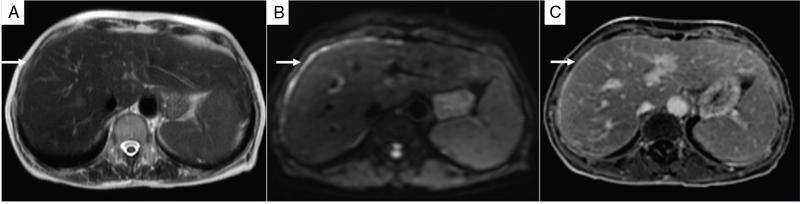

Shivsamb Jalkote, Slesha Bhalja, Disha Lokhandwala, Mansi Jantre, Karthik Ganesan Peritoneum is involved in a diverse group of primary as well as secondary pathologies ranging from the infective/inflammatory spectrum to malignancies. Peritoneal diseases are both common and potentially life threatening, and yet often get neglected in routine evaluation, due to the complex peritoneal anatomy and sometimes subtle imaging manifestations. The radiologist forms an integral part of the multidisciplinary team dealing with peritoneal pathologies and hence, having a lucid understanding of peritoneal anatomy, pathways of disease spread and different treatment options is paramount for an accurate radiological analysis. All three major serosal cavities (pleural, pericardial and peritoneal) of the body are derived from a single coelomic cavity, which is lined by a continuous mesothelium. At 2 weeks of gestational age, during the gastrulation stage, the embryo is a trilaminar disc, composed of the endoderm, mesoderm and ectoderm. During this stage, the development of the coelomic cavity commences as a consequence of morphological changes in the mesodermal cells leading to a coalition of the intercellular spaces. Peritoneum originates from mesoderm with its parietal layer developing from somatic mesoderm and visceral layer developing from splanchnic mesoderm. Initially, the peritoneum is an empty sac into which the growing gut tube protrudes (at 3 weeks of gestational age), resulting in the formation of the dorsal mesentery (formed by the fusion of two layers of the splanchnopleuric mesoderm) by which the gut tube is suspended lengthwise. The mesodermal cells opposed to the gut tube represent the future visceral peritoneum and those lining the body wall and the septum transversum form the future parietal peritoneum. Analogously, the ventral mesentery originates from the mesoderm of the septum transversum with the closure of the anterior abdominal wall, and, is short and not as extensive as the dorsal mesentery. The two mesenteries are aligned in the sagittal plane, subdividing the primitive peritoneum into right and left cavities, which are continuous anteriorly below the inferior edge of the ventral mesentery. With the development of various abdominal organs as buds from the gut tube, the capacity of the abdominal cavity diminishes, pushing the midgut loop into the umbilical cord. This physiologic herniation of the midgut takes place at the 6th week of gestation. Simultaneously, as the peritoneum drapes over the developing organs, there is compartmentalization of the cavity and a pattern of folds develops that eventually form the peritoneal ligaments. The majority of these ligaments arise from the ventral or dorsal mesentery. As the hepatic bud develops within the ventral mesentery, derivatives of the ventral mesentery can be divided based on their relation to the liver. The gastrohepatic ligament (lesser omentum) develops dorsally and the falciform, coronary, and triangular ligaments develop ventral to the liver. Conversely, the dorsal mesentery spans between the gut tube and the posterior abdominal wall, and the spleen and pancreatic tail develop within it. In congruence, it forms the gastrophrenic, gastrosplenic and splenorenal ligaments and peritoneal folds of the small and large intestines. As stated earlier, the dorsal mesentery has a relatively larger caudad extension and since the spleen develops in its upper portion, the rapidly growing mesentery beyond the spleen forms the greater omentum. Finally, the differential growth of the greater curvature of the stomach and the right hepatic lobe results in rotation of the abdominal organs and their mesentery, and the cephalad portion of the peritoneal cavity is divided into a larger ventral cavity, called the greater sac, which caudally communicates with the common peritoneal cavity, and a smaller dorsal cavity called the lesser sac. The key aspects of peritoneal development are summarized in Flowchart 8.6.1 and Fig. 8.6.1. Laparoscopy remains the gold standard in the assessment of peritoneal disease, however, it is an invasive technique, and has certain diagnostic limitations including the inability to assess parenchymal diseases, extraperitoneal diseases, and also has limited utility in the presence of adhesions. Hence laparoscopy is not recommended as the first-line modality and has been replaced by cross-sectional imaging in routine clinical practice. The role of imaging is primarily to assess disease burden in terms of volume and extent and to identify surgically nontreatable disease, which reduces open and shut laparotomies. Peritoneal metastatic disease burden is assessed using peritoneal carcinomatosis index (PCI) both surgically as well as using cross-sectional imaging, details of which will be discussed subsequently. CT, MRI and PET/CT are all commonly used imaging modalities, however, there is no singular universally accepted reference imaging standard for the peritoneal disease. In a recent meta-analysis evaluating the diagnostic performance of imaging in the detection of peritoneal metastasis (PM), authors concluded that MRI (DWI) and PET/CT show comparable diagnostic performance in gastrointestinal and ovarian cancer malignancies however the widespread availability of MRI makes it the more likely imaging modality of choice in the future. The results of this study are summarized in Table 8.6.1. Conventional imaging including radiography and barium studies have a poor diagnostic yield in evaluating peritoneal pathologies. Abdominal radiographs are usually restricted for identifying pneumoperitoneum and bowel obstruction in the setting of acute abdominal pain. Diffuse increase in radio-opacity of the abdomen, poor definition of soft tissue shadows (psoas, liver and spleen), bulging flanks along with medial displacement of small bowel loops from the properitoneal fat stripe are indirect markers of large ascites which can prompt further evaluation with ultrasonography. Indirect features of peritoneal disease on barium studies include mass effect and displacement of adjoining bowel loop, narrowing of bowel loop with bowel dilatation along with nodularity, spiculation, or tethering of adjacent mucosal folds or haustra with sacculation of the uninvolved contralateral border. Barium studies have fallen out of favour in routine radiological practice owing to the widespread use of cross-sectional imaging. Ultrasonography (US) is a readily available and relatively inexpensive imaging tool. Traditionally its role in the evaluation of peritoneal pathologies is limited as US beam gets strongly reflected at the interface of air and visceral structures which leads to obscuration of underlying structures. US remains the primary imaging modality in the evaluation of an acute abdomen and is useful in detecting of ascites, focal lesions and any focal abnormality at the site of tenderness. US has the unparalleled advantage of providing real-time assistance in performing imaging-guided procedures such as paracentesis and peritoneal biopsies. US can be used in characterization of focal lesions (as solid, solid-cystic and cystic) and assessment of internal vascularity using colour Doppler. Transvaginal US provides a good overview of pathologies involving pouch of Douglas besides the uterus and adnexa. Experienced and skilled sonologists can detect omental thickening, peritoneal nodules and small surface deposits using high-frequency transducer (Fig. 8.6.2). Endoscopic US allows assessment of diseases involving peritoneal ligaments besides assistance in a guided biopsy. The reported sensitivity, specificity and accuracy of EUS-FNA versus CT/MRI in detecting PM was 91% versus 28%, 100% versus 85% and 94% versus 47%, respectively. CT is the most commonly employed imaging modality in the evaluation of peritoneal pathologies due to its widespread availability, fast acquisition and high spatial resolution. Current generation multidetector CT scanners (64 slices and above) offer very thin collimation, leading to the acquisition of near isotropic volumetric data which allow reformations in coronal and sagittal images without any added imaging time. It is the modality of choice for preoperative staging in most primary abdominal and pelvic malignancies (e.g. stomach, appendix, ovary) owing to its ability to detect local and regional infiltration, nodal involvement and distant metastases. CT is also used to evaluate PCI and detect disease in critical and occult locations, thus significantly altering further management strategies. CT is the most common imaging modality used in postoperative surveillance and evaluation of postoperative recurrence. CT protocol includes administration of both enteric contrasts (oral and rectal) and intravenous contrast (Table 8.6.2). Optimal bowel distension is key as collapsed loops can mimic disease and also mask the serosal and endoluminal disease. Often, a CT scan of the chest is performed as an adjunct to rule out pleuroperitoneal/transdiaphragmatic dissemination. Helical (≥64 slice scanner) Dual energy scanner if available As thin as possible (≤1 mm) Same as section thickness without gap From xiphisternum to pubic symphysis Chest included if suspicion of thoracic involvement 1 L of positive oral contrast over duration of 60 minutes and 500 mL of positive rectal contrast on table before administration of IV contrast 1.5–2 mL/kg of nonionic contrast with high iodine concentration (≥ 300) at rate of 3–5 mL/sec Unenhanced imaging not recommended. Monophasic acquisition at 60 seconds usually sufficient in majority cases Arterial phase at 20 seconds acquired for arterial assessment Delayed phase in cases of ureteric obstruction, slow bowel transit and suspected leak. Axial 1 mm thickness, multiplanar reformats in coronal and sagittal planes at 1 mm MIP or 3D volumetric sections for vascular assessment There is a wide range of reported diagnostic accuracy (sensitivity ranging from 25% to 100%, specificity ranging from 78% to 100%) of CT in the assessment of PM depending on the expertise of the reader and scanner type. In general, key factors affecting CT sensitivity include the size of lesion, the region of affection and presence of ascites. 64 slice scanners with multiplanar reformations allow 100% sensitivity and positive predictive value in detecting lesions measuring >5 cm, which partly diminishes for lesions between 0.5 cm and 5 cm in size with sensitivity and positive predictive being 83% and 93%, respectively. It receives the most criticism in the evaluation of lesions < 0.5 cm with significantly low sensitivity and positive predictive value (43% and 76%, respectively). There is also a great degree of variation in sensitivity based on the anatomical location of the disease. In a study by Koh et al., the detection rates ranged from 8% to 67%, depending on the region involved; only the epigastrium exceeded 60%, with the small-bowel disease being the most poorly visualized (8%–14%). The sensitivity for tumour detection in epigastrium, greater omentum and under surfaces of the diaphragms was 60%–90%, while it was 50%–70% in the retroperitoneum and pelvis, and small bowel-mesentery involvement was detected in merely 20%–50% of cases. These are noteworthy findings, as small-bowel involvement has major implications on outcome and is one of the limiting factors for complete cytoreduction. Poor soft tissue resolution of CT doesn’t allow accurate differentiation between mucinous deposits from ascites. Administration of positive enteric contrast can mask calcified serosal deposits. DECT uses two separate x-ray energy spectra and allows characterization of tissues based on their differences in attenuation properties at different energies. Though the role of DECT in the assessment of abdominal pathologies is increasingly reported in the literature, there are very limited data available on its application in assessment of peritoneal pathologies. The combination of iodine overlay with conventional imaging has shown a better specificity in differentiating PM from benign peritoneal entities, and hence can be particularly useful in the postoperative setting. MR imaging offers excellent soft tissue resolution, multiplanar capabilities and avoids exposure to ionizing radiation, making it an attractive tool for evaluation of peritoneal diseases. MRI is better suited and can be problem solving in visualization of smaller lesions (<1 cm) and assessment of relatively concealed areas such as subphrenic, mesenteric and bowel serosa. Unenhanced T1- and T2-weighted images can show larger peritoneal deposits and masses but are relatively insensitive for the depiction of smaller lesions. The combination of diffusion-weighted imaging (DWI) and delayed gadolinium-enhanced MR imaging is considered the most accurate technique for detecting peritoneal tumours (Fig. 8.6.3). MRI protocol for assessment of peritoneum has been detailed in Table 8.6.3. In a study by Low RN et al., MRI PCI correctly categorized tumour volume in 91% of patients compared to surgical PCI, as opposed to 50% with CT. In addition, MRI demonstrated per site sensitivity of 95%, specificity of 70% and accuracy of 88%, while CT showed a corresponding per site sensitivity of 55%, specificity of 86% and accuracy of 63%. MRI PCI has also shown to have better prediction of intraoperative burden of disease for invasive appendiceal and peritoneal mesothelioma histologies as compared to CT-PCI. *This general imaging protocol is based on 3 T MRI Siemens system, covers both abdomen and pelvis. Protocol is modified depending on primary disease and type of scanner. Low RN. Preoperative and surveillance MR imaging of patients undergoing cytoreductive surgery and heated intraperitoneal chemotherapy. Journal of gastrointestinal oncology. 2016 Feb;7(1):58. The higher cellularity of majority of peritoneal nodules results in restriction of water movement and corresponding high signal intensity on DW images. On the higher b-value images, bowel contents are suppressed and the serosal and peritoneal tumours become hyperintense. DWI is also useful to demonstrate associated lymphadenopathy, hepatic and osseous metastases. In a study by Zhang et al., in PC of colorectal carcinoma, DWI demonstrated sensitivity of 69.4%, 91.3% and 100% for lesions measuring <0.5 cm, 0.5–5.0 cm and >5 cm, respectively. The overall sensitivity, specificity and accuracy of DWI for the detection of peritoneal tumours were 80.3%, 84.5% and 82.1%, respectively. DWI/MRI is also superior in demonstrating lesions involving small bowel wall, with an accuracy of 92%–95% versus 48% for CT. Reported negative predictive value of DWI for small bowel serosal metastases is 100%. Whole-body DWI/MRI was highly accurate for the prediction of inoperability (PPV 100%, NPV 90.3%) and was capable of detecting metastases both inside and outside the abdominal cavity. Peritoneal tumours enhance slowly and are best depicted on the final set of images obtained about 5 minutes following gadolinium administration. The increased conspicuity of these enhancing peritoneal tumours improved detection of small tumours that are often missed on CT scans. For this reason, perfect breathhold is essential while obtaining the final set of images and if images are acquired later, contrast that has diffused into the ascitic fluid can obscure smaller lesions. The high-contrast conspicuity of fat-suppressed and delayed gadolinium-enhanced MRI makes it the imaging modality of choice in depicting subcentimetre deposits (including those measuring <5 mm), and also deposits in anatomically concealed sites (e.g., subphrenic, mesenteric and bowel serosa). Gadolinium-enhanced MRI has higher sensitivity in detecting peritoneal lesions <1 cm which is about 85%–90% compared to 22%–33% for CT. Despite the clear superiority of MRI over CT, the major detractors against MRI are the long exam times and the higher expense burden. Longer acquisition times can lead to motion artefacts related to respiration and bowel peristalsis compromising detection of smaller lesions. MRI is contraindicated in patients with pacemakers, cochlear implants and claustrophobic patients with some exceptions. DW-MRI is less sensitive in special histological subtypes such as signet ring cell and mucinous adenocarcinoma due to their limited restricted diffusion. The combined use of FDG-PET with anatomical CT imaging, provides the added benefit of qualitative and semiquantitative metabolic analysis (Fig. 8.6.4). PET/CT has an established role in staging of most of the primary tumours of the chest, abdomen and pelvis. It is also helpful in assessing malignant ascites or PM of an unknown primary. In disseminated malignancies, it can localize the optimal site for biopsy depending upon metabolic activity of the lesion. PET/CT should be used selectively in preoperative assessment of patients with large tumour volumes and poor prognostic histologies being considered for CRS and HIPEC to rule out extra abdominal metastases. It can also detect extraabdominal metastases, including mediastinal and supraclavicular nodes, and other organ sites, such as bone and brain. It can also detect nodal involvement in normal-sized lymph nodes seen on conventional cross-sectional imaging. PET/CT also plays a role in disease surveillance and assessment of response to neoadjuvant chemotherapy. This is particularly relevant in malignancies where anatomical changes are so small that measurement of size change alone becomes unreliable and also in differentiating between residual/recurrent disease and postoperative changes after CRS and HIPEC. Besides oncological indications, PET/CT is also helpful in assessment of benign and inflammatory diseases to evaluate disease extent and also localize the site for biopsy. In cases of pyrexia of unknown origin, PET/CT has often been employed to demonstrate unsuspected peritoneal disease. Utility of PET/CT in peritoneal disease assessment is limited in developing counties due to its higher cost burden and lower accessibility. Certain histological subtypes such as mucinous and signet ring cell carcinomas show low FDG uptake making PET/CT less sensitive. Low metabolic uptake in these subtypes is thought to be due to low tumour cell density, higher content of metabolically inert mucin and lack of expression of glucose transporter Glut-1. This is more relevant in context of colorectal malignancy where mucinous carcinoma and signet ring cell carcinoma more frequently metastasize to the peritoneum compared to adenocarcinoma (48%, 51% and 20%, respectively). PET/CT is prone to artefacts caused by misregistration between the CT and PET images which can lead to inaccurate assessment of certain regions such as dome of diaphragm and structures adjoining the urinary bladder, making the detection of pelvic implants difficult due to partial volume effects. Implants against the small bowel and mesentery may be obscured by the physiological metabolic activity of bowel. Pretreatment PET/CT demonstrates a higher accuracy than CT for nodal and metastasis staging but has limited sensitivity to detect PM, especially when there is small-volume disease as only 13.6% of the nodules less than 0.5 cm were correctly identified by PET/CT. Table 8.6.4 summarizes role of different imaging modalities for assessment of peritoneal diseases. Peritoneum is the largest serosal membrane in human body with surface area of about 2.2 m2. It is composed of parietal and visceral layers which are continuous with each other, with parietal peritoneum lining the coelomic cavity and visceral peritoneum lining the visceral organ (Fig. 8.6.5). The peritoneum essentially minimizes friction, resists infection and stores fat, allows free movement of the abdominal viscera which gets restricted in presence of adhesions. Peritoneum acts as first line of defence in controlling disease spread, and, it exudes fluid and cells in response to injury or infection (peritonitis), to wall off or localize infection. In natural states, intraperitoneal spread of infection is limited by lymphoid aggregates and stomata on both the peritoneal layers. Omentum is commonly known as policeman of abdomen as it migrates to the site of infection and isolates affected area from healthy tissues. Iatrogenic violation of peritoneum following surgery can lead to recurrence along the operative incision scar sites and along the vaginal cuff following hysterectomy in pelvic malignancies. The parietal peritoneum is supplied by nerves (e.g. phrenic and thoracoabdominal) to the adjacent body wall, and is predominantly very sensitive to pain, which explains the typical referred shoulder pain from upper abdominal pathologies such as gall stones and pancreatitis. The visceral peritoneum is insensitive to pain and responds mainly to stretching. These two layers encompass a potential space, called the peritoneal cavity which contains approximately 50–75 mL of clear serous fluid. Peritoneal cavity is a closed space in males while in females it communicates with extraperitoneal pelvis through ostia of fallopian tubes allowing transport of ovum. This communication serves as natural route for ascending spread of sexual transmitted disease from genital organs into peritoneal cavity leading to pelvic inflammatory disease and uncommonly perihepatitis (Fitz–Hugh–Curtis syndrome). The invaginations of the peritoneum result into formation of three different types of structures namely ligaments, omentum and mesentery (Figs. 8.6.6–8.6.9) which serve as bridges that permit blood, lymph vessels and nerves to reach the viscera. Ligaments are double folds of peritoneum that connect one organ to another organ or to the abdominal wall and are named usually after the respective viscera. The liver, for example, is connected to the diaphragm by the falciform ligament, coronary ligament and right and left triangular ligaments. Mesenteries are double folds of peritoneum that suspend intestine to the posterior abdominal wall (retroperitoneum) such as the small bowel mesentery, transverse and sigmoid mesocolon. Omentum are double folds of peritoneum that extends from the stomach to other organs and include the greater and lesser omentum. Table 8.6.5 summarizes the peritoneal ligaments in abdomen and pelvis. In medical school days, the anatomy textbooks traditionally divided abdomen and pelvis into tricompartmental model comprising of peritoneal cavity, retroperitoneum and extraperitoneal spaces. This model is good for basic understanding of anatomy and confinement of certain disease processes but fails to explain spread of diseases from retroperitoneum to peritoneum besides spread of some disease processes within peritoneal cavity itself. Considering these shortcomings of conventional description of anatomy, the unifying concept of subperitoneal space has evolved in literature and is getting accepted increasingly. As per this concept, abdomen and pelvis are divided in two spaces peritoneal cavity and subperitoneal space which are separated from each other by peritoneum. Subperitoneal space (Fig. 8.6.10) is large anatomically continuous potential space which connects peritoneal cavity with retroperitoneum. It constitutes the subserosal areolar tissue and fat tissue lining the inner surfaces of the peritoneum and the abdominopelvic musculature. The omentum, ligament and mesentery are the interconnecting peritoneal folds building the subperitoneal space. All the abdominal and pelvic organs along with their vascular, lymphatic and nervous supplies are situated within subperitoneal space. With this concept, we want to correct the common misconception of intraperitoneal organs as in strict terminology there is no organ within the peritoneal cavity itself. It is imperial to understand differences between peritoneal and subperitoneal spaces as these are mutually exclusive spaces having distinct patterns of disease spread which we will discuss in subsequent sections. In resting state, peritoneal cavity is collapsed and thus not visible on routine imaging. Peritoneal cavity usually gets distended due to disease processes composed of fluid, air or masses. The peritoneal cavity is divided into two parts: the greater sac and the lesser sac which communicate with each other via an epiploic foramen (of Winslow). The greater sac forms main peritoneal cavity and extends from the diaphragm down into the pelvis. The lesser sac is small diverticulum and lies between stomach and pancreas. For better understanding, abdominal peritoneal cavity is divided into supra- and inframesocolic compartments, communicating with pelvic peritoneal cavity which is further divided by other peritoneal folds and reflection (Flowchart 8.6.2, Figs. 8.6.10 and 8.6.11). Supramesocolic compartment (Fig. 8.6.12) is situated between the diaphragm and transverse mesocolon. It is arbitrarily divided into right and left supramesocolic peritoneal spaces, which can be further subdivided into a number of subspaces by upper abdominal organs and peritoneal ligaments. Right supramesocolic space is divided into three subspaces: right subphrenic space, right subhepatic space and lesser sac. Right subphrenic space is partially separated from right subhepatic space by right triangular ligament. Right subphrenic space is situated between right hemidiaphragm and right lobe of liver (superior, anterior and right lateral surfaces). It is limited posteriorly by the coronary ligament and medially by the falciform ligament with the latter separating it from the left subphrenic space. Right subhepatic space is situated inferior to right lobe of liver and has anterior and posterior components. Anterior component is limited inferiorly by transverse mesocolon whereas the posterior component extends anterior to right anterior perirenal fascia. Posterior component of right subhepatic space is commonly known as hepatorenal pouch (of Morrison) and forms most dependent site in supine position, thus being a common site of fluid accumulation. The right subhepatic space freely communicates with right subphrenic space superiorly and right paracolic gutter inferiorly. Lesser sac (also known as omental bursa) is situated superior to the transverse mesocolon, anterior to pancreas and posterior to the lesser omentum, stomach and gastrocolic ligament. Lesser sac (Fig. 8.6.13) communicates with right subhepatic space (of greater sac) via epiploic foramen which is bounded by IVC posteriorly, free margin of hepatoduodenal ligament anteriorly, D1 (first part of duodenum) caudally and caudate lobe of liver rostrally. Division of lesser sac into smaller superior compartment (superior recess) and larger inferior compartment (inferior recess and splenic recess) is accomplished by prominent crescentic gastropancreatic fold (peritoneal fold overlying common hepatic and left gastric artery) which extends from neck of the pancreas to the upper part of lesser curvature of stomach. The superior recess is situated to the right of midline above pancreas and posterior to lesser omentum. It surrounds the medial aspect of the caudate lobe and superiorly into the fissure for the ligamentum venosum. Splenic recess extends to splenic hilum, and is limited by gastrohepatic ligament (anterior), gastrosplenic ligament (lateral) and splenopancreatic ligament (posterior). Inferior recess is located to left of midline, separates stomach from the pancreas and transverse mesocolon. In few cases, an infrapancreatic part can be seen due to persistence of inferior recess within the greater omentum or due to downward bowing of transverse mesocolon. Left supramesocolic space is wider than right supramesocolic space and is limited above by left hemidiaphragm and below by transverse mesocolon and phrenicocolic ligament. Left supramesocolic space (subphrenic part) is medially separated from right supramesocolic space by falciform ligament and inferiorly from left paracolic gutter by phrenicocolic ligament. It is divided into four communicating subspaces: anterior left subphrenic space, posterior left subphrenic space, anterior left perihepatic space and posterior left perihepatic space. All these spaces communicate with each other. The definitions of the boundaries of these spaces vary in literature. Anterior left subphrenic space is situated between gastric fundus and left hemidiaphragm. Posterior left subphrenic space (also known as perisplenic space) surrounds spleen. Anterior left perihepatic space is situated between anterosuperior aspect of left lobe of liver and left hemidiaphragm. Posterior left perihepatic space (also known as gastrohepatic recess) is situated between inferior aspect of left lobe of liver and lesser omentum. Inframesocolic compartment (Fig. 8.6.14) extends below transverse mesocolon to the level of pelvic brim and is divided into large central part and smaller paracolic part (lateral recesses). Central portion of inframesocolic compartment is unequally divided by obliquely oriented small bowel mesentery leading to formation of smaller right inframesocolic compartment and larger left inframesocolic compartment. Right inframesocolic space terminates at the ileocaecal junction and does not communicate with pelvis. Left inframesocolic space is in communication with pelvic peritoneal spaces except at the sigmoid mesocolon attachment which offers partial barrier. Peritoneal recesses on the posterior abdominal wall lateral to the ascending and descending colon form right and left paracolic gutters respectively. Both paracolic gutters communicate freely with pelvic peritoneal spaces. Right paracolic gutter is deeper than left gutter and is in free communication with right supramesocolic space. Left paracolic gutter is partially limited from left supramesocolic space due to presence phrenicocolic ligament. Pelvis constitutes about one-third of the total volume of the peritoneal cavity and is most dependent part in both supine and erect positions. Inferiorly peritoneum drapes over fundus of urinary bladder, anterior and posterior surface of uterus and upper posterior vagina in females and anterolateral surface of the upper rectum leading to formation of different peritoneal spaces. The urinary bladder subdivides pelvis into anterior and posterior paravesical spaces. The anterior paravesical space is further compartmentalized by remnant of the urachus (median umbilical ligament), the obliterated umbilical arteries (medial umbilical ligament), and the lateral umbilical ligaments (inferior epigastric vessels) into five fossae: the right and left lateral and medial inguinal fossae and the supravesical fossa. The supravesical space is seen in midline with medial and lateral inguinal fossae placed on either side. The supravesical space lies above urinary bladder between the two medial umbilical folds, is usually occupied by small bowel loops and fundus of distended urinary bladder. Just lateral to the supravesical space is the medial inguinal fossa, located between the medial and lateral umbilical folds. The femoral ring is located inferolaterally and hence ascitic fluid in the medial inguinal fossa can extend into the femoral canal. Finally, the lateral inguinal fossa is located between the lateral umbilical fold and parietal peritoneum (which reflects over the vas deferens or round ligament). It usually contains the cecum or ileum on the right and sigmoid colon on the left. Extension of ascitic fluid into the inguinal canal can occur through the deep inguinal ring, located anteromedial to the lateral inguinal fossa. The posterior paravesical space is a larger recess situated between the urinary bladder and rectum. In women, uterus further divides it into smaller vesicouterine and larger rectouterine spaces. The vesicouterine space is located between the urinary bladder and uterus and is formed as the peritoneum drapes the uterine body and fundus and then runs over the urinary bladder (along its posterosuperior surface). It is continuous with the supravesical space anteriorly and its depth varies with the degree of urinary bladder distension. The rectouterine pouch (of Douglas) is delimited anteriorly by the uterus and broad ligaments and posteriorly by the rectum. Lateral to this cul-de-sac on either side are the uterosacral ligaments that run from the sacrum to the uterine cervix that separate the rectouterine pouch from the laterally located ovarian fossae. In men, the rectovesical pouch is formed as the peritoneum runs from the rectum to the posterior surface of the bladder. Posteriorly, the peritoneal reflection from the upper rectum runs to the pelvic sidewalls, forming right and left pararectal fossae, which vary in size with the degree of rectal distension. Analogous to the uterosacral ligaments in women, the rectovesical space is restricted by sacrogenital folds on either side, which extend from the urinary bladder to the sacrum. The rectovesical space and rectouterine space (pouch of Douglas) form most dependent areas in both in supine and standing positions in males and females, respectively (both in supine and standing positions). The key aspects of pelvic peritoneal spaces are summarized in Flowchart 8.6.3, Figs. 8.6.15 and 8.6.16. Peritoneal recesses represent small pockets or fossae in the peritoneal cavity bounded by folds of peritoneum and possibly represent developmental aberrations. Knowledge of these recesses is important as they can serve as pathways for internal hernias. Multiple peritoneal folds may surround fourth part of duodenum (D4) and duodenojejunal junction forming duodenal recess. Six major duodenal recesses include superior, inferior, paraduodenal, retroduodenal, duodenojejunal and mesentericoparietal recess. The superior duodenal recess is situated to the upper left side of fourth part of duodenum (D4) behind the superior duodenal fold at L2 level. Inferior mesenteric vein is situated behind lateral end of superior duodenal fold. Inferior duodenal recess is situated on left of D4 below DJ flexure and behind the inferior duodenal fold at L3 level. Inferior duodenal recess often exists in association with superior duodenal recess. Reported incidence of superior and inferior duodenal recesses is about 40%–50% and 70%–75%, respectively. Paraduodenal recess is seen on left side and slightly behind D4 bounded anteriorly by paraduodenal (falciform fold). Right free margin of paraduodenal fold contains the inferior mesenteric vein and an ascending branch of the left colic artery. This recess is seen in about 2%–3.8% cases and is site for left paraduodenal hernia. Retroduodenal recess as the name suggests situated behind the third and fourth parts of the duodenum and in front of abdominal aorta. Its orifice is bounded anteriorly by duodenoparietal fold. Retroduodenal space is largest among all the duodenal recesses and is seen in about 2.5% cases. Duodenojejunal recess is situated between the duodenojejunal flexure and root of transverse mesocolon, hence also known as mesocolic recess. Its boundaries include pancreas (superior), left renal vein (inferior) and left kidney (left). Its opening lies between two peritoneal folds, is directed inferiorly and to the right. Duodenojejunal recess is seen in about 20% cases and is almost never associated with other duodenal recesses. Mesentericoparietal recess is situated below third part of duodenum and behind the upper part of the mesentery. Its opening is bounded anteriorly by the fold of mesentery raised by the superior mesenteric artery. This recess is most rare among all with incidence of about 1%. It is the site for right paraduodenal hernia. The key aspects of duodenal recesses are summarized in Table 8.6.6 and Fig. 8.6.17. Peritoneal folds adjoining cecum result in formation of four main recesses: superior ileocaecal recess, inferior ileocaecal recess, retrocaecal recess and paracolic recess (Fig. 8.6.18). Surgically these recesses are important as they can be sites for internal herniation (except for paracolic sulci) or site of abscess formation in complicated appendicitis. Superior ileocaecal recess is bounded in front by the vascular fold of the cecum (containing anterior caecal vessels), behind by the ileal mesentery, below by the terminal ileum and on the right by the ileocaecal junction with its opening on left. Inferior ileocaecal recess is bounded in front by the ileocaecal fold (bloodless fold of Treves), above by the terminal ileum and its mesentery, to the right by the caecum, and behind by the upper part of the mesoappendix with its opening on left. Retrocaecal recess is bounded in front by posterior wall of cecum (and sometimes the proximal ascending colon), behind by the parietal peritoneum (posterior abdominal wall), and on either side by two caecal folds (parietocolic folds). Retrocaecal recess is largest among all the caecal recesses with its opening inferiorly and often contains appendix. Paracolic sulci represent variable one or more shallow lateral depressions in the peritoneum investing the cecum usually within the right paracolic gutter. This recess lies behind and inferior to the apex of inverted V-shaped root of sigmoid mesocolon with orifice opening inferiorly. Posteriorly, it is limited by parietal peritoneum of covering the left ureter at its iliac vessel crossing. This recess can be variable in size ranging from dimple to a small fossa in majority of the cases usually admitting little finger. It forms most common site of sigmoid mesocolon hernia. It can also be involved by peritoneal fluid and metastatic disease. Peritoneal and subperitoneal spaces are mutually exclusive spaces having distinct patterns of disease spread. Different pathways of the intraabdominal and extraabdominal disease spread are summarized in Table 8.6.7.

MRI

Diffusion-weighted MRI imaging

Contrast-enhanced MRI (CE MRI)